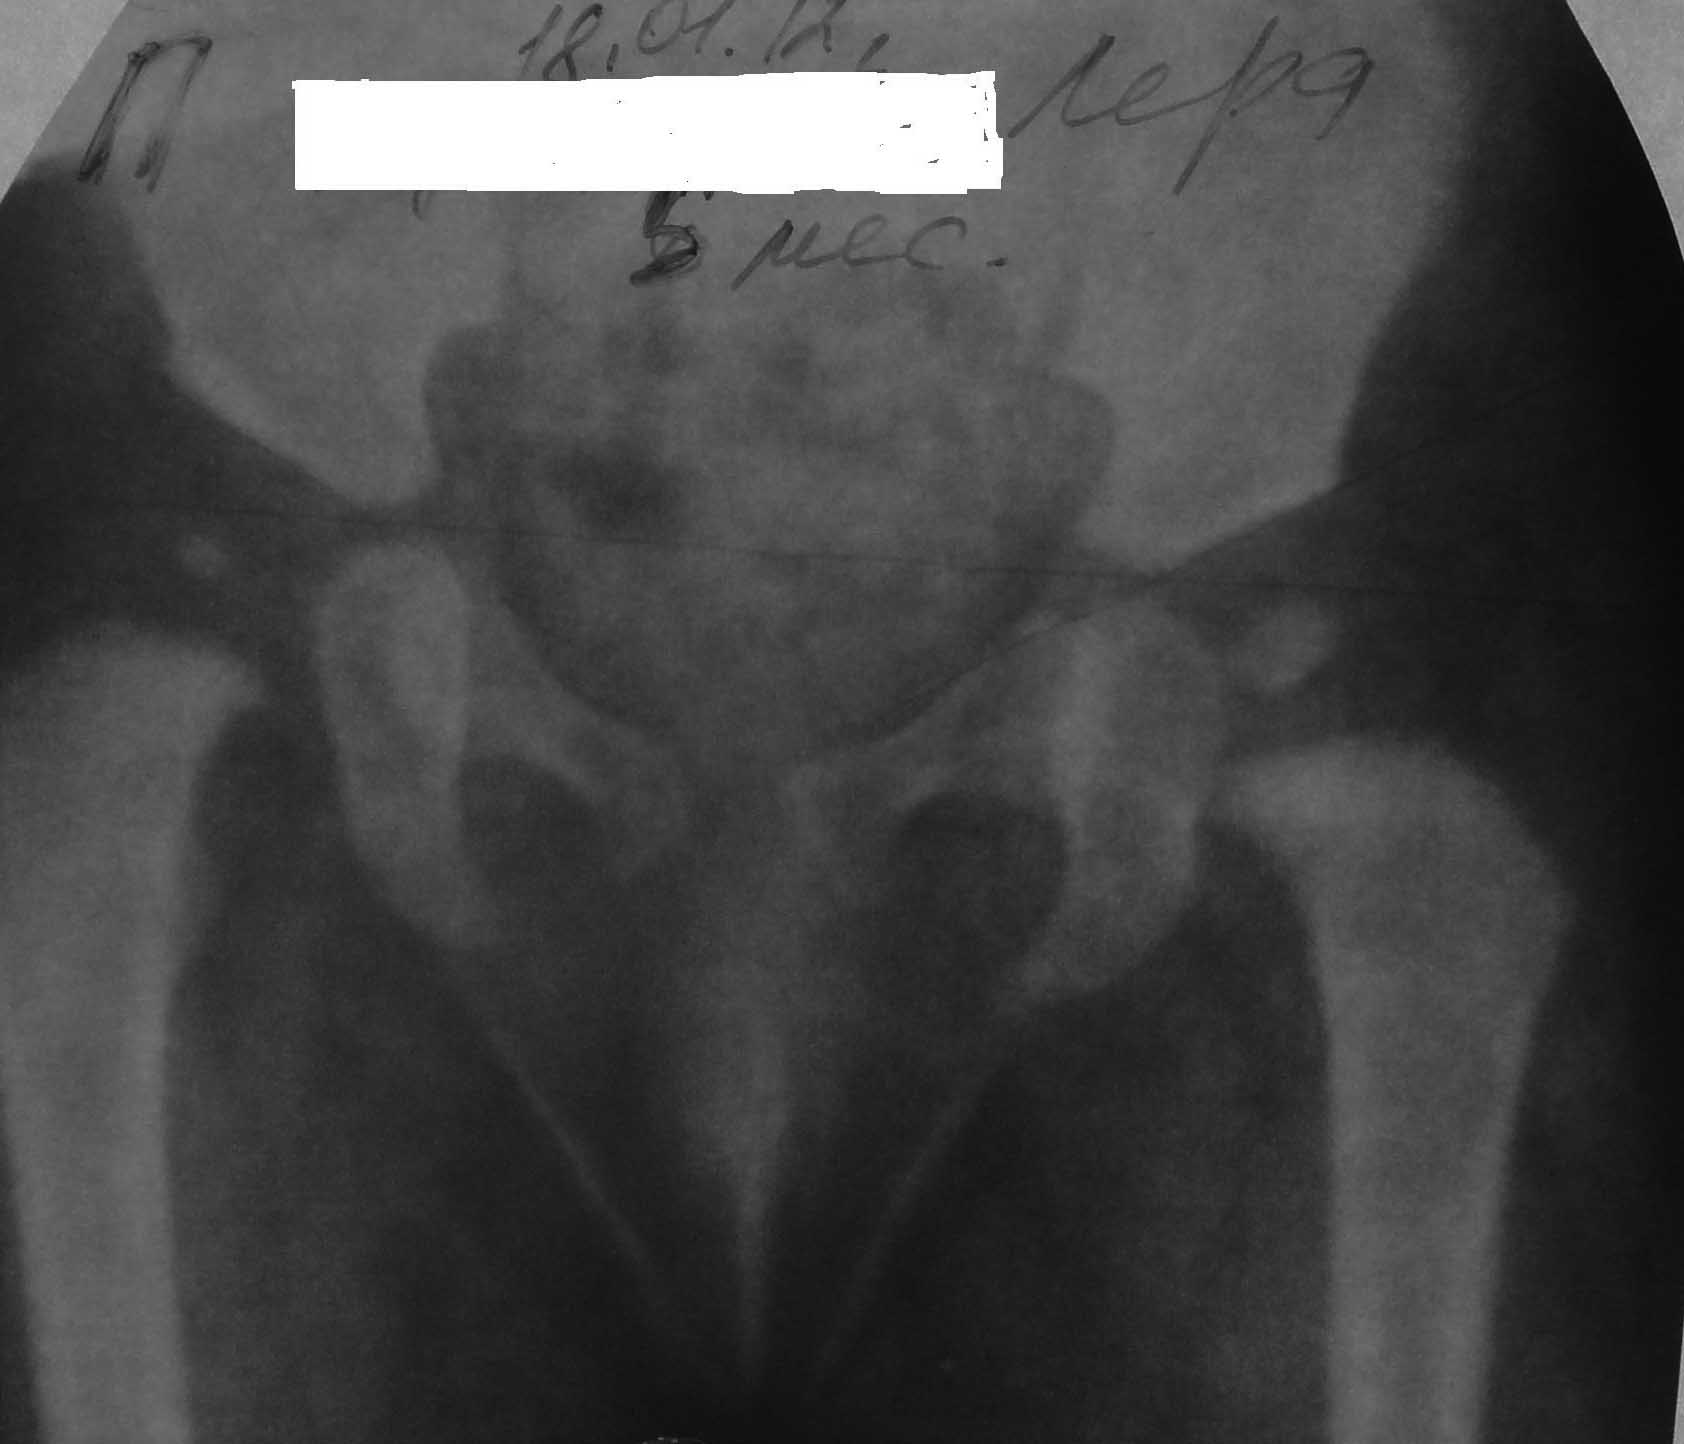

Ребенок моих знакомых девочка 6мес. от первой беременности первых родов, родила в срок

,доношенная ,маму беспокоила ассиметрия бедренных складок обратились ко мне.Объективно

ребенок правильного телосложения,движения в конечностях в полном объёме,длина нижних

конечностей равная,дополнительная кожня складка на правом бедре ,небольшая ассиметрия

половой щели ,ассиметрия ягодичных складок ,отведение в т/б суставах удовлетворительное

справа несколько в меньшем объёме.Рекомендовал рентгенографию.Вот такая ситуация ,ваше

мнение по тактике лечения?